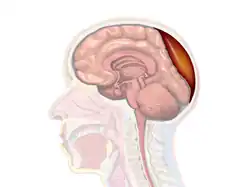

Epidural hematoma is when bleeding occurs between the tough outer membrane covering the brain (dura mater) and the skull.[4] When this condition occurs in the spinal canal, it is known as a spinal epidural hematoma.[4]

Epidural hematomas usually appear convex in shape because their expansion stops at the skull's sutures, where the dura mater is tightly attached to the skull. Thus, they expand inward toward the brain rather than along the inside of the skull, as occurs in subdural hematomas. Most people also have a skull fracture.[3]